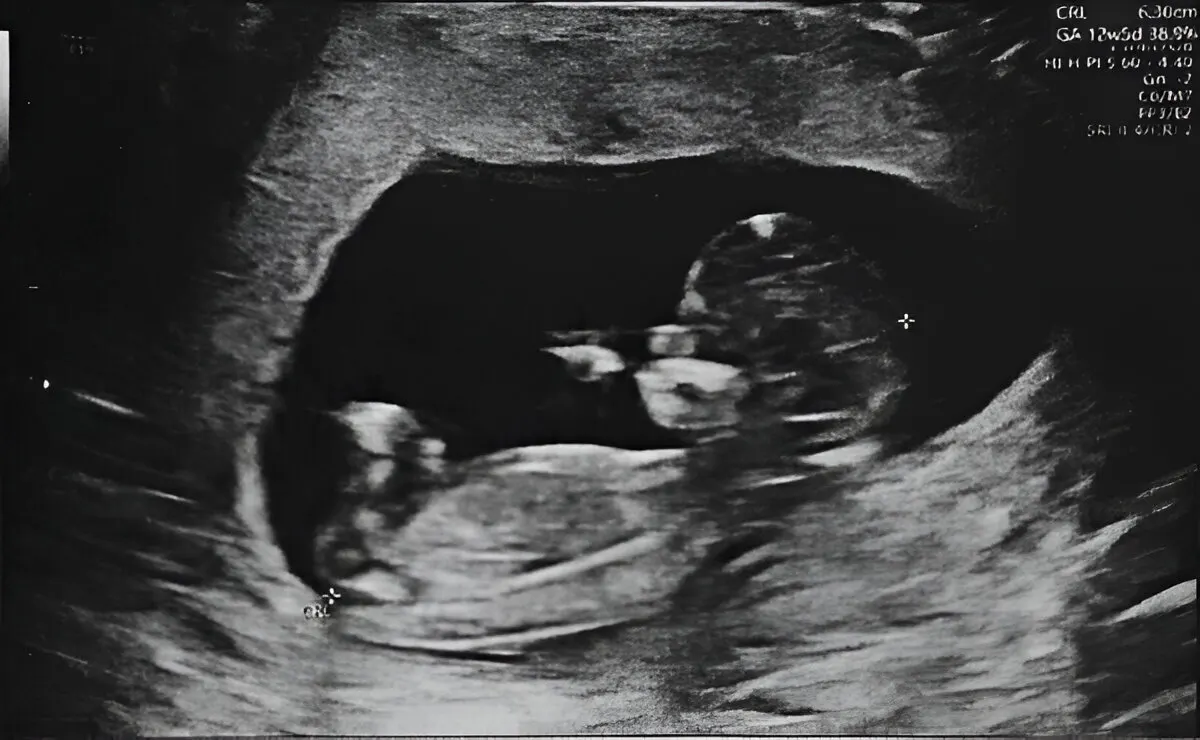

Combining NT Scan with Doppler for Comprehensive Fetal Health Evaluation

Combining NT scan with Doppler gives a complete fetal health check. First, it detects early problems like heart defects, growth issues, and placental insufficiency. Henotic Diagnostics in Kharghar, Navi Mumbai, offers accurate risk assessments and timely care. Together, NT scan and Doppler ensure fetal well-being and peace of mind. Our experienced female radiologists provide compassionate, precise care. We follow ISUOG protocols and NABL standards. Additionally, we specialize in 3D Uterine Artery Doppler, 3D Umbilical Artery Doppler, 3D MCA Doppler, and 3D Ductus Venosus Doppler in Kharghar & Navi Mumbai. Similarly, we provide Uterine Artery Doppler, Umbilical Artery Doppler, MCA Doppler, Placental Doppler, and 3D Power Doppler Angiography in Kharghar & Navi Mumbai for accurate results. As a result, you get trusted results for monitoring fetal oxygen flow and maternal blood supply assessment. Additionally, we offer affordable, expert Obstetrics (OBS) Doppler in Kharghar & Navi Mumbai. Book your Best Obstetrics (OBS) Doppler Near You or the Best Obstetrics (OBS) Doppler in Kharghar & Navi Mumbai today.